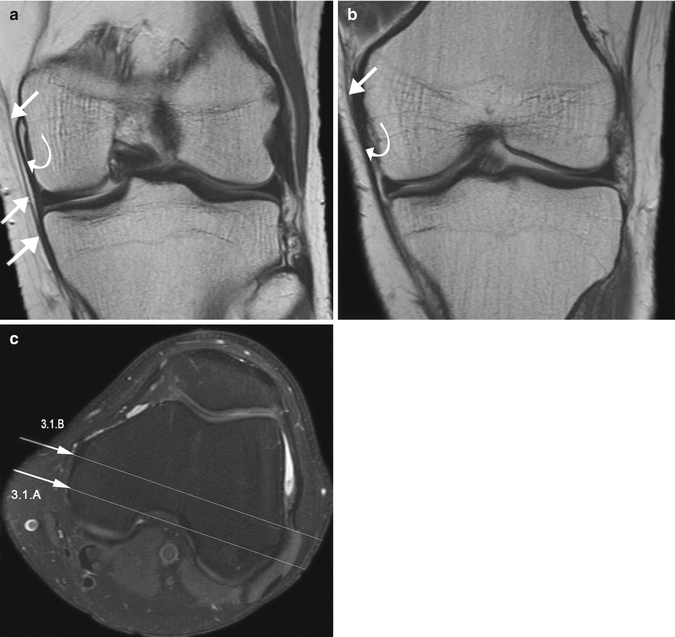

Medial Collateral Ligament (MCL) and Medial Supporting Structures

From radiologykey.com

Medial Collateral Ligament (MCL) and Medial Supporting Structures Old Mcl Injury Radiology Other signs include a wavy form of. Reference is made to the movement of the tibia with respect to the femur during stress testing. (minor sprain) high signal is seen medial. The most obvious sign of medial collateral ligament injury is its discontinuity in case of a partial or complete tear. In one specimen, the tibial portion of the mcl. Old Mcl Injury Radiology.